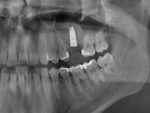

Sinus Lift With Simultaneous Implant

Sinus Lift